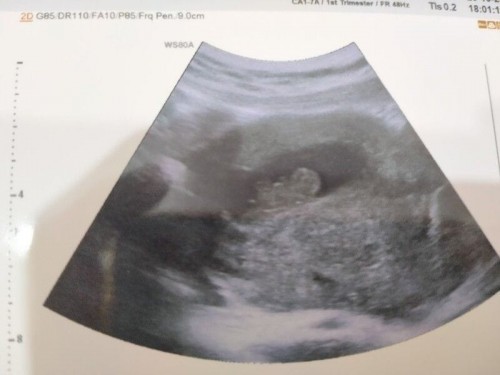

ตอนนี้ได้11week แต่ไปซาวด์แล้วน้องเสียไปเมื่อ4สัปดาห์ก่อนเลยจำเป็นต้องยุติการตั้งครรภ์ อยากทราบว่าถ้ายุติการตั้งครรภ์ที่โรงพยาบาลของรัฐ มีค่าใช้จ่ายอะไรไหมคะ ถ้ามีมากน้อยแค่ไหน อยากทราบจากแม่ๆที่มีประสบการณ์ค่ะ#ขอบคุณล่วงหน้านะคะ #ขอบคุณสำหรับคำตอบค่ะ